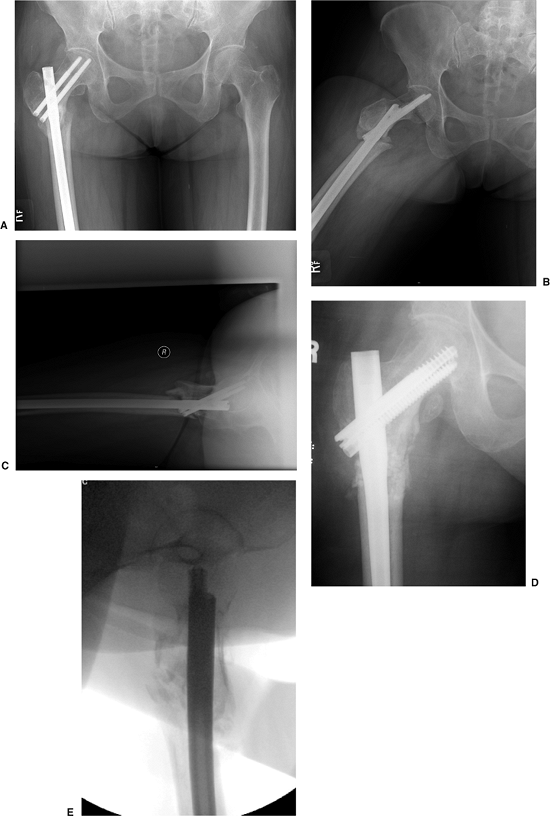

fall down stairs, sustained a Russell-Taylor IIB, closed,

subtrochanteric fracture (Fig. 20.47). She

underwent closed TriGen reconstruction nailing with a trochanteric

portal nail. Her fracture united, and she regained independent

ambulatory status by 4 months after surgery. This case represents the

advantages of a trochanteric portal with the MINIT in comminuted

fracture situations.

nondisplaced femoral-neck fracture that was treated with multiple

screws. Two months after the surgery, she fell again, sustaining a

subtrochanteric fracture. Her injury was revised with a piriformis

entry nail but in a malreduced position. After 1 year, her fracture was

successfully revised with a percutaneous osteotomy, autogenous bone

grafting with DBM extender, and TriGen Intertan (Smith & Nephew,

Memphis, TN) nailing in a reduced position with the channel reamer

technique (Fig. 20.48).

Figure 20.47. A,B Russell Taylor IIB subtrochanteric fracture from a low-level fall. C,D. Reduction and stabilization with trochanteric antegrade TriGen nail in reconstruction mode with MINIT.

Figure 20.48. A–C.

Preoperative nonunion of subtrochanteric fracture with malreduction of proximal fragment. Note poor bone apposition because of the malreduction. D,E. Postoperative appearance with percutaneous osteotomy and grafting with reduction of deformity and fixation through use of TriGen Intertan system. |